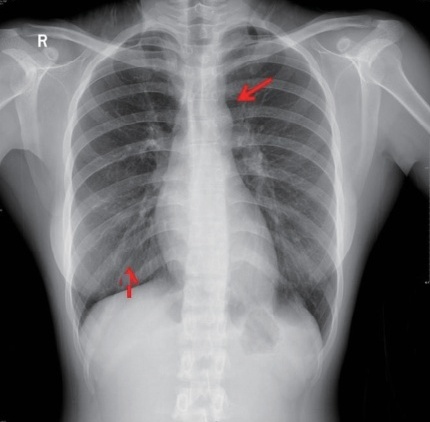

病史摘要:患者主因“检查发现肺部阴影5年”就诊。5年前当地医院体检发现肺部结节,无不适症状。1周前于杭州市肿瘤医院检查,右肺上叶后段结节倾向于MIA或AIS,余两肺微小结节建议年度复查,附见脂肪肝、左肾结石。患者起病来一般情况良好,有高血压病史10年,口服药物控制。 诊疗过程:查体未提及。影像显示2021 - 2025年结节有变化,考虑早期肺癌可能性大,鉴别诊断包括支气管腺瘤、原位癌伴肺泡